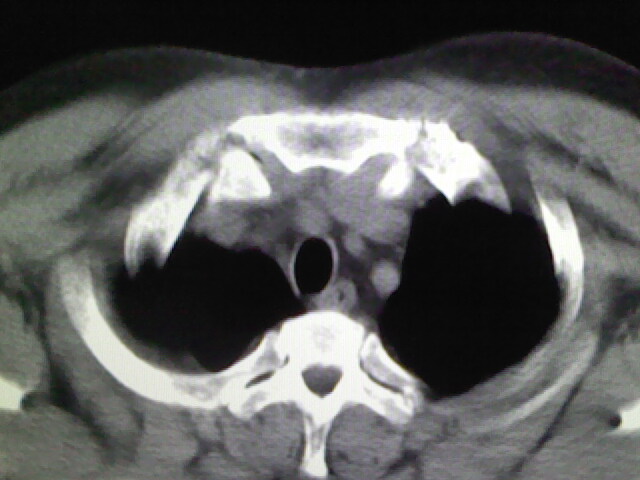

标题: CT17932:临床怀疑肺栓塞

男,34岁,自觉右侧胸痹,胸闷3天余

左上肺局限片状透光度增强区,肺纹理稀少,可考虑局限性肺气肿。

右侧肺动脉似见密度稍低影,请在机器的薄层上再看看有没有充盈缺损。

左上肺局限性肺透光度减低,肺纹理稀少;这虽然符合早期肺栓塞的改变,但与局限性肺气肿难以鉴别。

书上讲早期肺栓塞就是表现肺透光度减低,肺纹稀少。